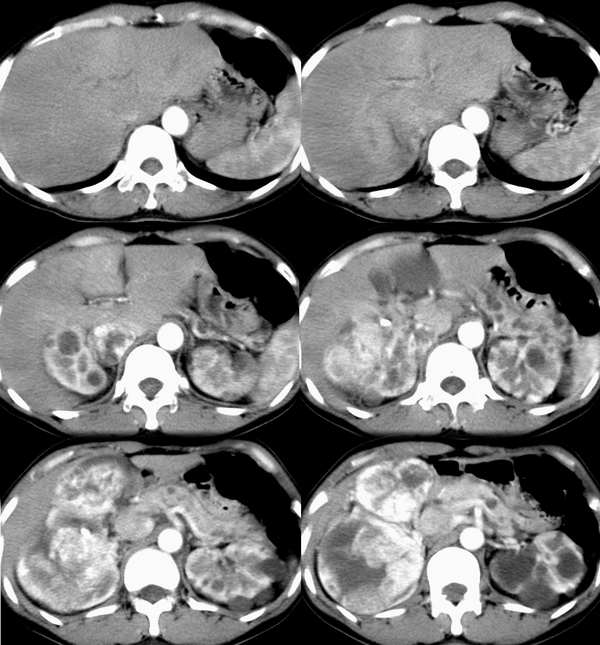

动脉期

静脉期

右肾体积增大,形态失常,其内可见多发低密度影,增强后动脉期病灶实质明显强化,低密度区未见强化,静脉期病灶呈等密度,考虑右肾癌,左肾多发囊肿,多囊胰

右肾体积增大,形态失常,其内可见多发低密度影,增强后动脉期病灶实质明显强化,低密度区未见强化,静脉期病灶呈等密度.

考虑1右肾囊性癌,2左肾多发囊肿,3多囊胰可能?